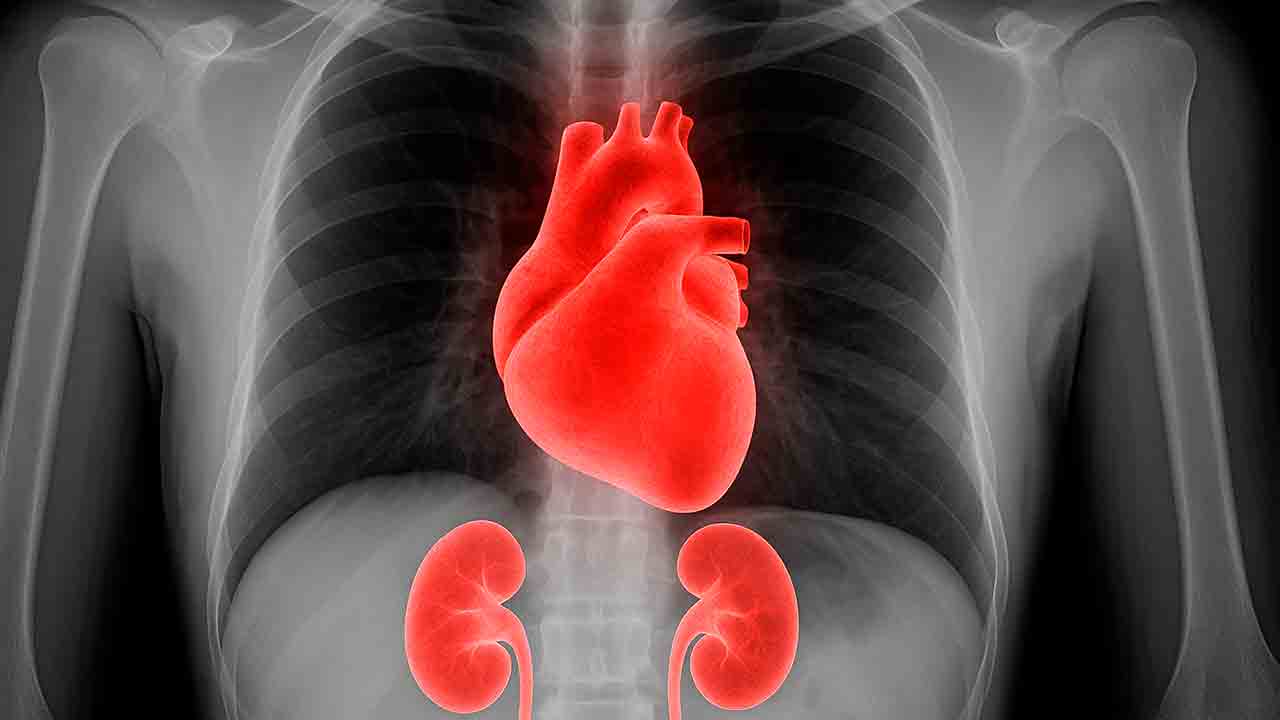

Órgãos mais afetados

Rins (insuficiência renal)

Coração (arritmias, insuficiência cardíaca)